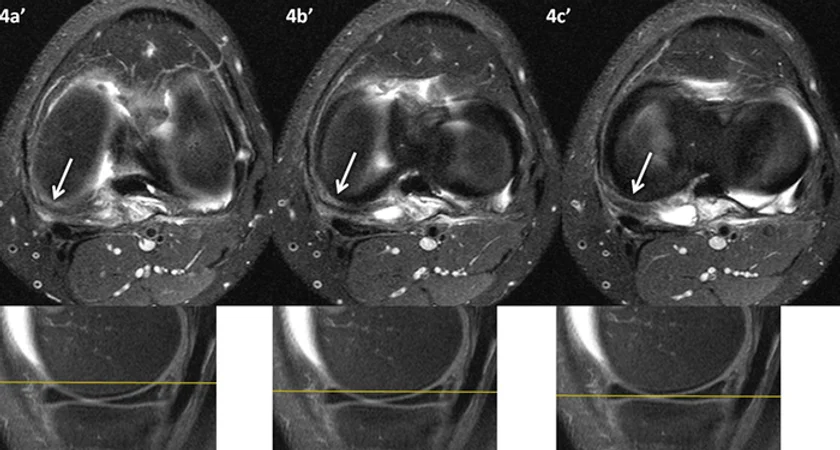

Figura 4 (a-c): Imagens de RM no plano transversal na ponderação T2 com supressão de gordura no nível da interlinha articular femorotibial.

Figura 4 (a-c)’: Imagens de RM no plano transversal na ponderação T2 com supressão de gordura no nível da interlinha articular femorotibial. Abaixo imagens de referência no plano sagital mostrando a lesão hipersinal na periferia do corno posterior do menisco medial e na cápsula posteromedial (setas brancas).